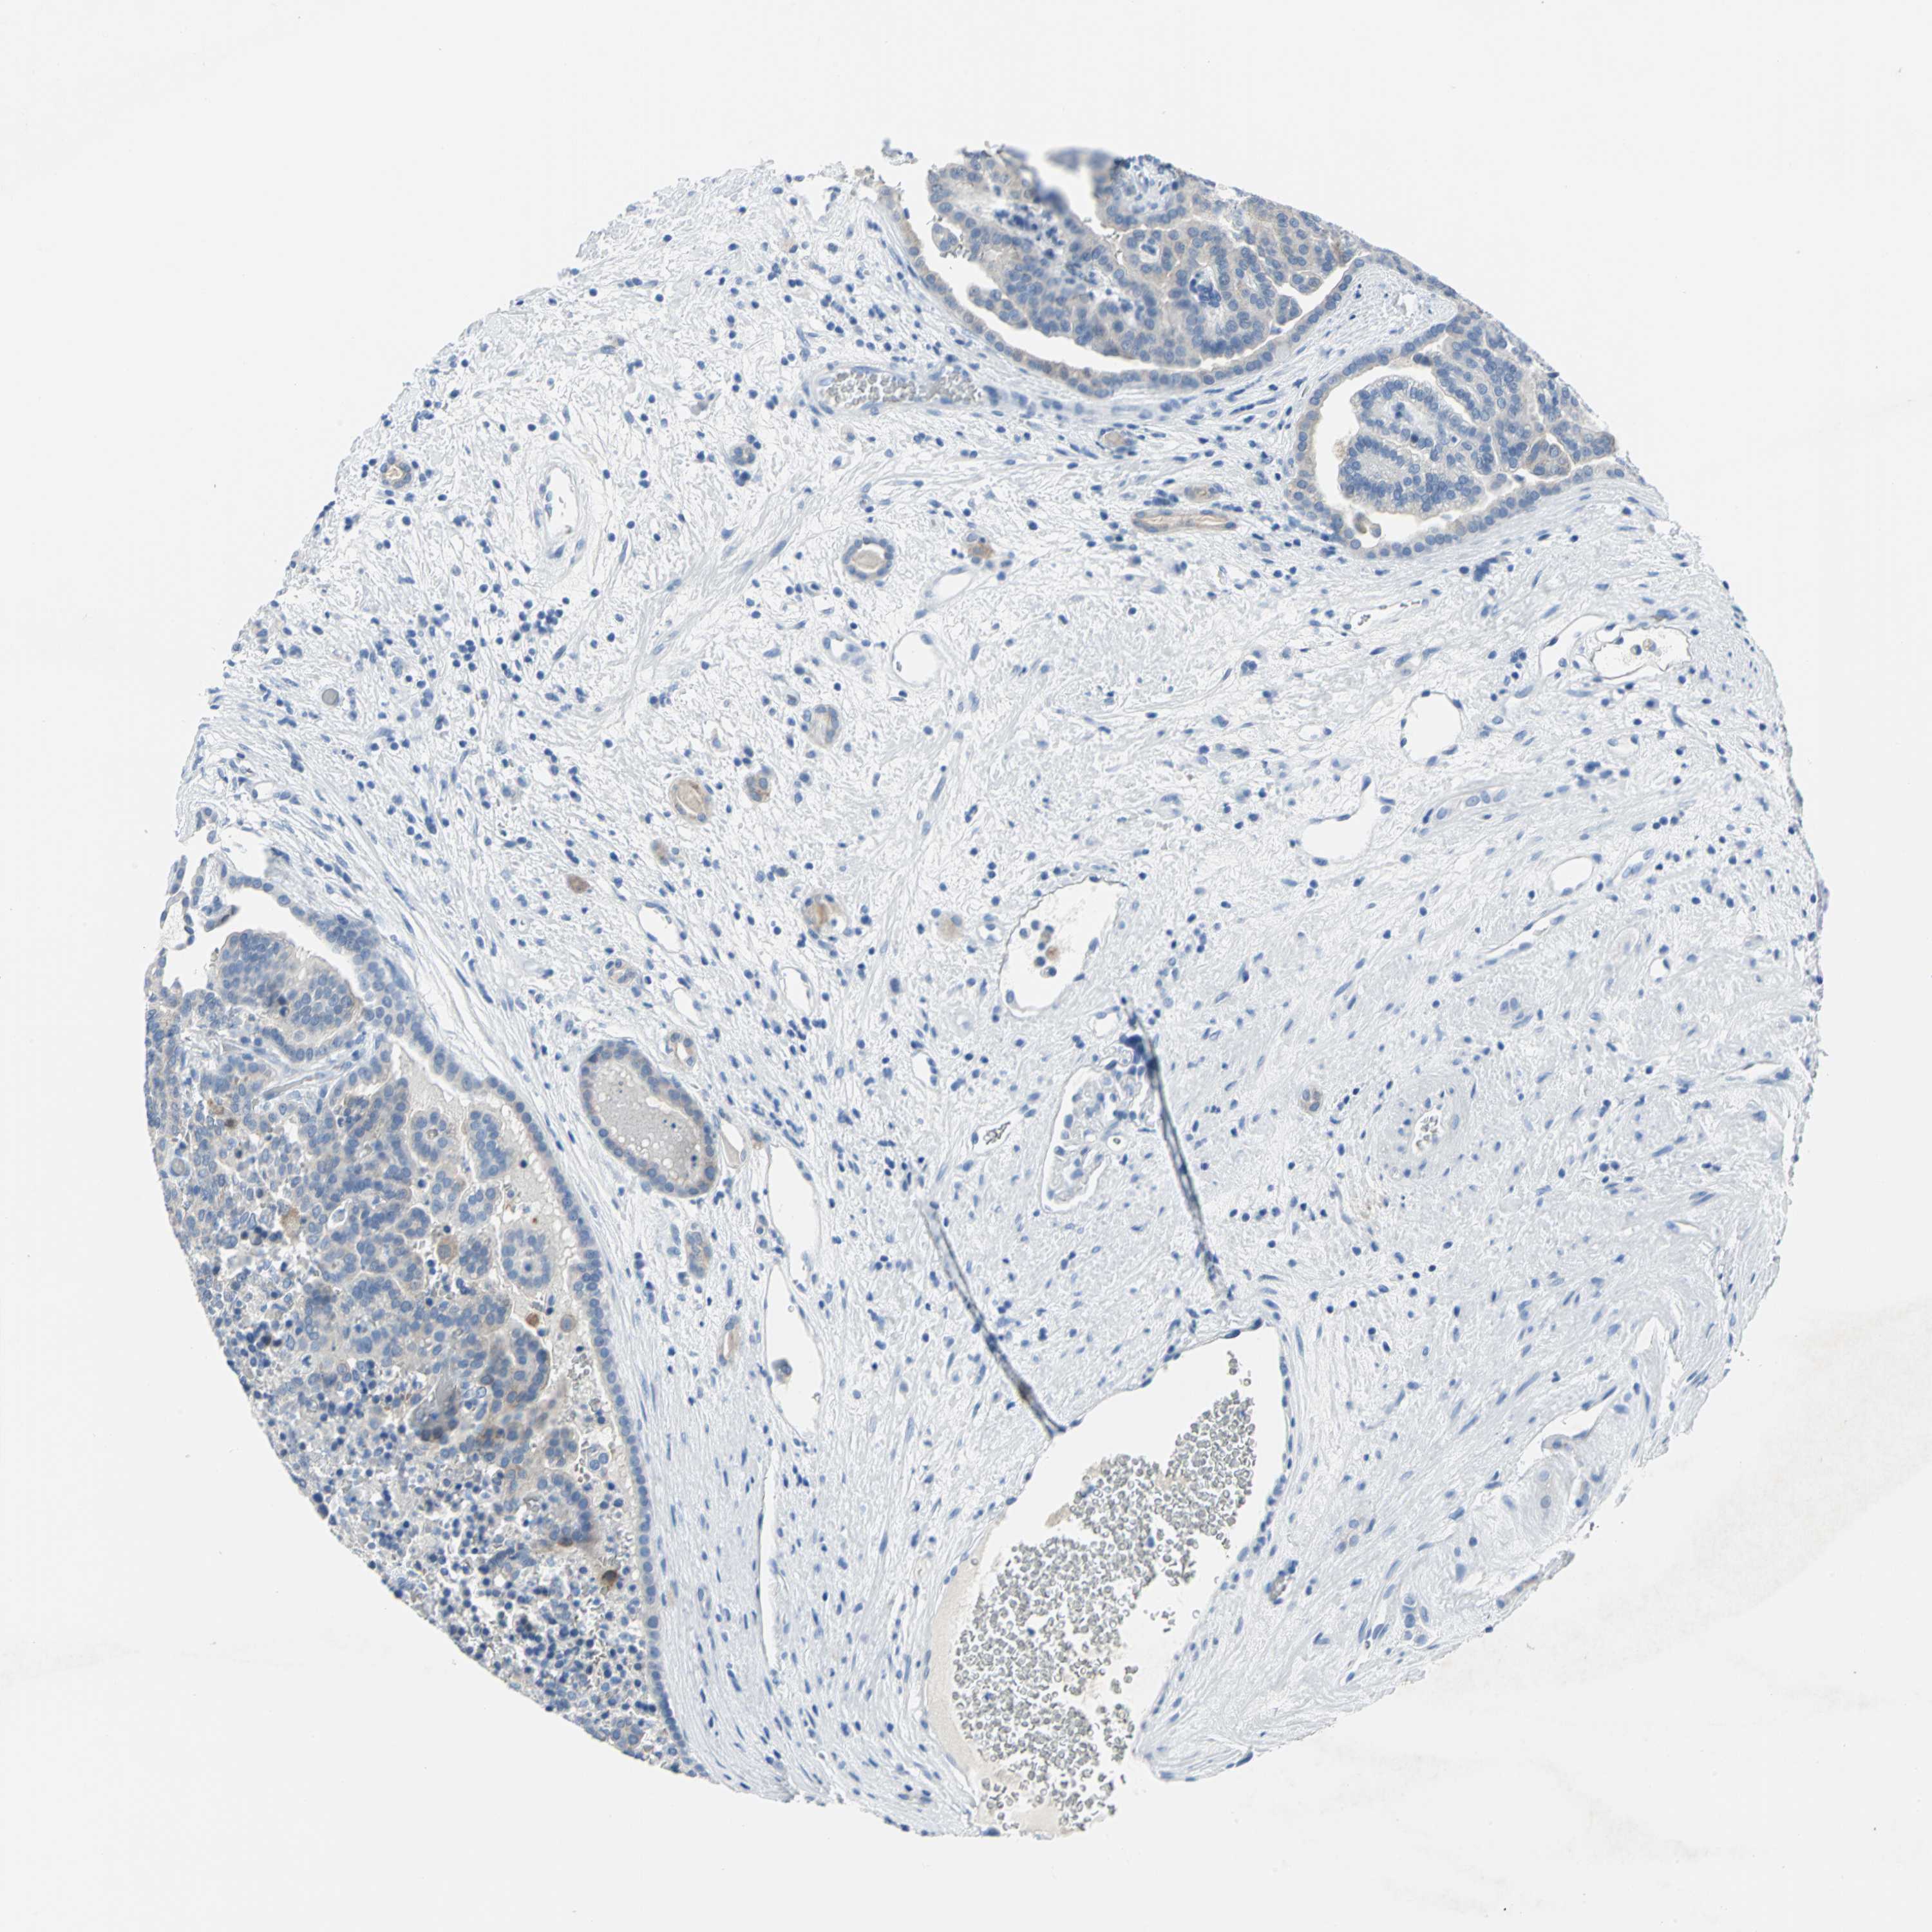

KIDNEY RENAL PAPILLARY CELL CARCINOMA (TCGA) - Interactive survival scatter ploti

The Survival Scatter plot shows the clinical status (i.e. dead or alive) for all individuals in the patient cohort, based on the same data that underlies the corresponding Kaplan-Meier plots. Patients that are alive at last time for follow-up are shown in blue and patients who have died during the study are shown in red.

The x-axis shows the expression levels (FPKM) of the investigated gene in the tumor tissue at the time of diagnosis. The y-axis shows the follow-up time after diagnosis (years). Both axes are complimented with kernel density curves demonstrating the data density over the axes. The top density plot shows the expression levels (FPKM) distribution among dead (red) and alive patients (blue). The right density plot shows the data density of the survived years of dead patients with high and low expression levels respectively, stratified using the cutoff indicated by the vertical dashed line through the Survival Scatter plot. This cutoff is automatically defined based on the FPKM cutoff that minimizes the p-score. The cutoff can be changed by dragging the vertical line or by entering a cutoff value in the square labeled "Current cut-off".

Under the Survival Scatter plot the p-score landscape (black curve; left axis) is shown together with dead median separation (red curve; right axis). Dead median separation is the difference in median mRNA expression between patients who have died with high and low expression, respectively. It is calculated as follows: median FPKM expression of dead patients with high expression - median FPKM expression of dead patients with low expression. This is intended to aid the user in visually exploring custom cutoffs and the associated p-scores and dead median separation.

Individual patient data is displayed and can be filtered by clicking on one or more of the category buttons on the top of the page. Categories describing expression level and patient information include: high, low, alive, dead, female, male and tumor stages. The scale of the x-axis can be toggled between linear and log-scale by clicking on the "x log" button. Mouse-over function shows TCGA ID, patient information and mRNA expression (FPKM) for each patient.

& Survival analysisi

Kaplan-Meier plots summarize results from analysis of correlation between mRNA expression level and patient survival. Patients were divided based on level of expression into one of the two groups "low" (under cut off) or "high" (over cut off). X-axis shows time for survival (years) and y-axis shows the probability of survival, where 1.0 corresponds to 100 percent.

SFN is not prognostic in Kidney Renal Papillary Cell Carcinoma (TCGA)